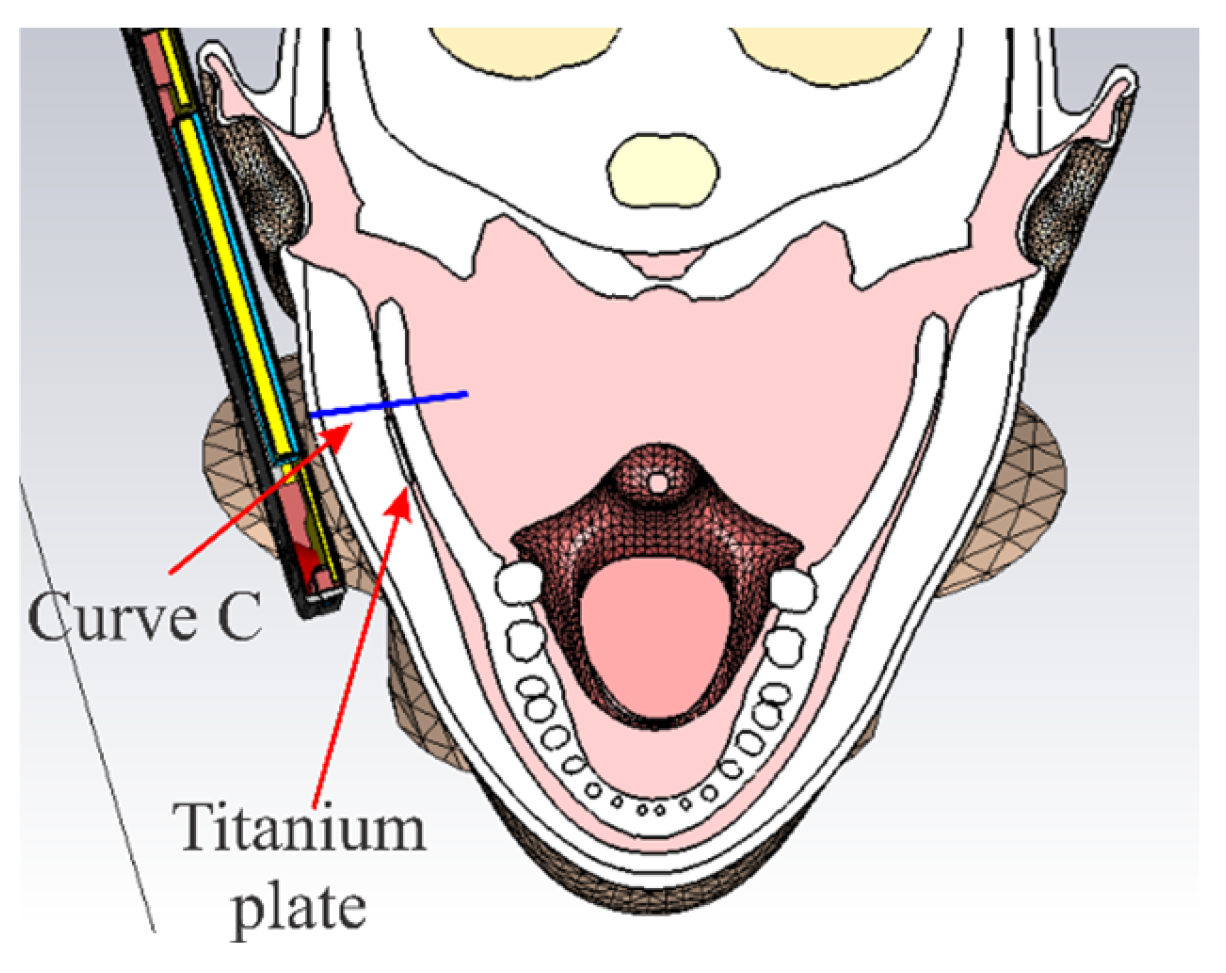

2.3. 3D Models of Titanium Plates and Screws

2.4. 3D Model of a Mobile Phone